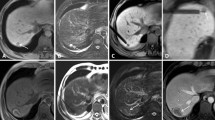

Representation after ablation

Instantly after ablation, central ablation area showed long oval, back and low signal around the antenna. Peripheral ablation area showed slightly hyperintense or isointensity in liver with clear or fuzzy boundary. A hypointensity ring was around the boundary on T1WI (Fig. 5A). Ablation area showed oval and low signal around the antenna on T2WI. A hyperintensity ring was around the hypointensity (Fig. 5B). Ablation area showed large oval and gray signal around the antenna on contrast-enhanced images. A hypointensity ring was around the ablation area. Another hyperintensity ring was outside, mapping the extent consistent with the ablation zone in T2WI (Fig. 5C,D).

Imaging characteristics after microwave ablation.

The ablated area represented a thin oblong hypointense oval around the antenna on T1W images (A) and thick oval hypointense with hyperintense surroundings on T2-weighted images (B). On contrast-enhanced T1-weighted images, the ablated area is represented by a thin line hypointense in the center, while enhancement of the ablated area was hypointense (C,D).

After ablation, the ablated area represented a thin, oval hypointense area around the antenna on T1W images and a thick oval hypointense with surrounding hyperintense area on T2W images. On contrast-enhanced T1W images, the ablated area represented a thin hypointense line in the center, with enhancement of the ablated area and hypointense surrounding area (Fig. 5). T2W and contrast-enhanced T1W clearly mapped the ablated area with distinct boundaries, while T1W was not suitable for mapping the ablated area.